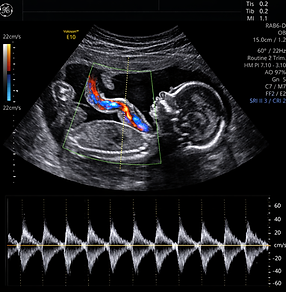

Imágenes Especializadas

En FEMSALUD contamos con una sección especializada dedicada a brindarte información detallada sobre los diversos tipos de imágenes ginecológicas y obstétricas que realizamos. Nuestro compromiso es ofrecerte estudios precisos y confiables, con tecnología de punta y personal altamente capacitado, para acompañarte en cada etapa de tu salud femenina y reproductiva.